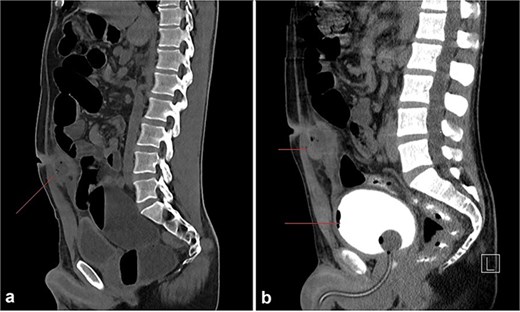

Lab tests showed an elevated white blood cell count of 14 000/mm3. A CT scan of the abdomen was requested, which scan revealed a dilated cecum filled with fecal matter, mildly dilated small bowel loops, and a fluid-filled, thick-walled cystic lesion measuring approximately 3.6 × 3 × 4.6 cm at the level of the umbilicus (Fig. 1a). The lesion, which contained a few tiny air locules and appeared to communicate with the umbilicus, did not show a clear connection to underlying bowel loops. A retrograde cystourethrogram was performed, showing an intact urinary bladder wall with no communication with the cystic lesion (Fig. 1b). The urinary bladder was mildly thickened, and no other significant abnormalities were noted in the abdominal and pelvic organs.

(a) A round to oval shaped, thick walled, fluid filled cystic lesion (34 HU) measuring ~3.6 × 3 × 4.6 cm is noted at the level of the umbilicus, subjacent to the rectus abdominus muscles; it appears to be in communication with the umbilicus. Few tiny air locules are noted within. (b) Retrograde cystourethrogram showing an intact urinary bladder with mild diffuse thickening of the wall. No communication can be seen between the abscess cavity and the bladder.